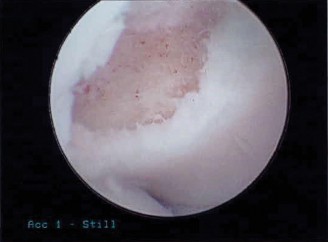

The patient undergoes conservative management consisting of rest, anti-inflammatory medications, and physical therapy. After six months, he is still not able to return to play and has progressively worsening symptoms with attempted throwing. He has a moderate elbow effusion as well as a 20-degree flexion contracture. An elbow MRI arthrogram is obtained and shown (Fig. 2–112). He elects to proceed with elbow arthroscopy. Intraoperative arthroscopic images are shown (Figs. 2–113 and 2–114).

Figure 2–112

Figure 2–113

Figure 2–114

Which of the following is the most commonly reported complication of elbow arthroscopy?

The correct answer is (D). The overall reported rate of transient and permanent complications after elbow arthroscopy is around 10% and is much higher than the rate after knee and shoulder arthroscopy (1–2%). The overall most commonly reported complication is prolonged drainage or erythema around portal sites. The lateral portal sites are susceptible to this issue as the joint is relatively subcutaneous in this area, and there is scant tissue to act as a barrier. Deep infection, while being the most serious postoperative complication, is relatively rare (0.8%). In one series, the rate of transient neurological injuries was found to be 2%. These result from compression, local anesthetic injection, and direct trauma. A thorough understanding of the neurovascular anatomy of the elbow is crucial to achieve proper portal placement. Loss of elbow motion was reported in approximately 1% of cases and is usually minor (less than 20 degrees). Objectives: Did you learn...? Recognize the clinical and radiographic presentation of elbow osteochondritis dissecans?